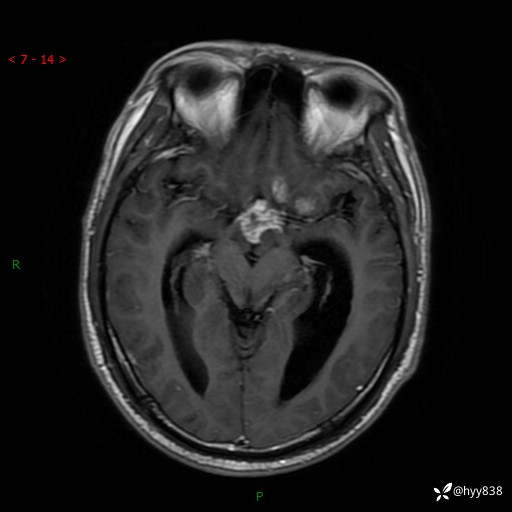

颅脑MRI平扫+增强